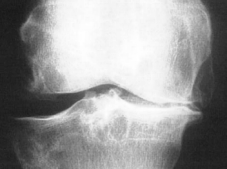

Bei der Arthrose (Bild rechts Kniegelenksarthrose) ist die mechanische Eigenschaft der Gelenkflüssigkeit erheblich beeinträchtigt. Diese kann dadurch die Pufferfunktion nicht mehr erfüllen. Die mechanische Belastung des Gelenkes nimmt zu, der Knorpel wird überlastet. In weiterer Folge treten Schmerzen, Entzündungen und Bewegungseinschränkungen auf.